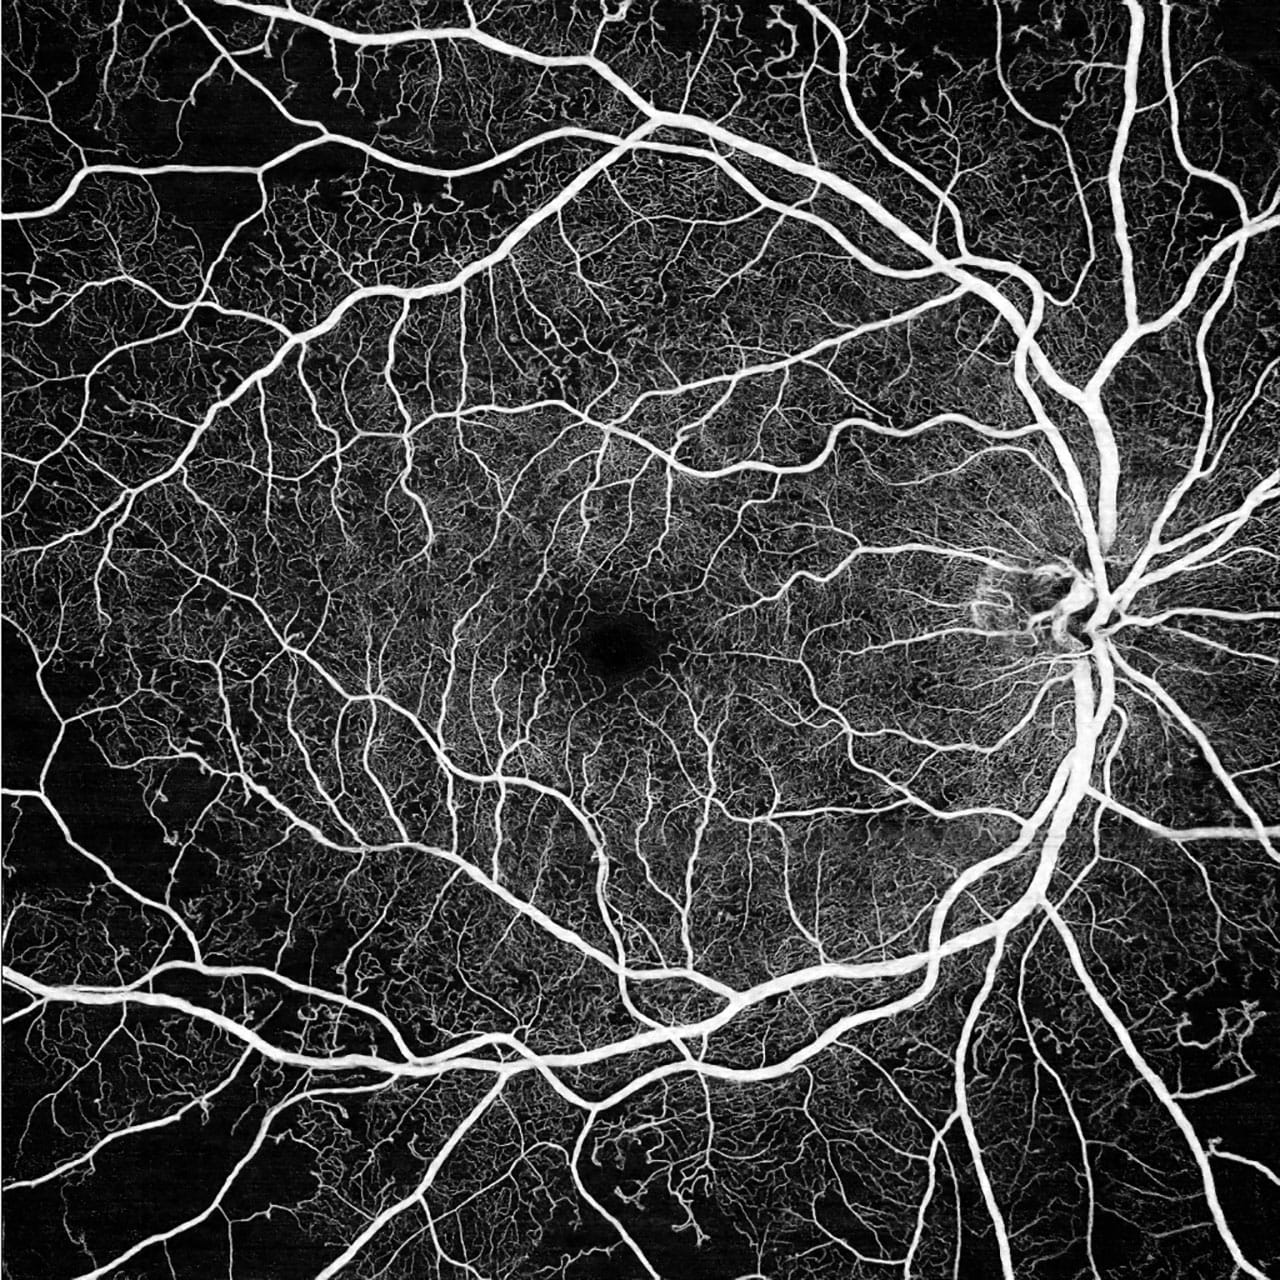

Learn More →Medical Retina

Anti-VEGF injection therapy and photodynamic treatment for wet AMD, diabetic retinopathy, and retinal vein occlusion — led by a recognized authority in PDT and a rising generation of retina specialists.

Learn More →Vitreous & Surgical Retina

Retinal tear and detachment repair, vitrectomy for epiretinal membrane and macular hole, and surgical management of complex vitreoretinal conditions.